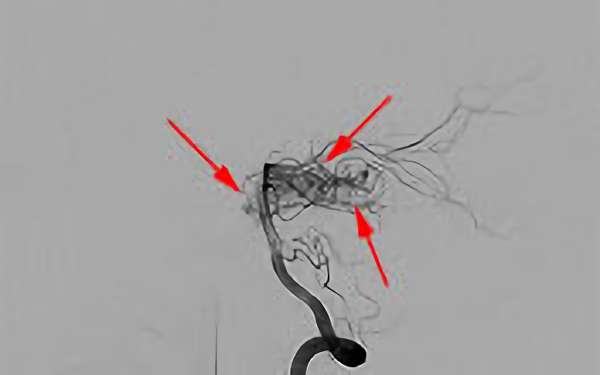

'26年3月

出血性脳動静脈奇形

10代

院内外来

No.1620 手術前

No.1620 手術中

No.1620 手術後